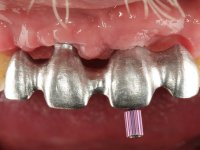

Primeira Fase

Foram feitas as extrações das raízes dos dentes 2.1 e 2.2 porque estavam a incomodar. Após 3 meses de cicatrização fez-se o exame imagiológico e estudo implantar para colocação do implante no local do 2.1.Foi colocado um implante de 4.1mm de diâmetro por 10mm de altura, colocado ao nível ósseo. Passados 2 meses após a cirurgia implantar, foi feita a segunda cirurgia para colocação de um parafuso de cicatrização. Foi feita a impressão ao implante com técnica de moldeira aberta com silicone de dupla viscosidade um mês após. No laboratório foi confecionada uma infraestrutura metálica para uma ponte de 2 elementos aparafusada ao implante. Esta infraestrutura apresentava 2 apoios palatinos para ajudar a estabilizar os dentes 1.1 e 2.3 a recuperar do traumatismo. Recuperados os dentes, os apoios poderiam ser retirados. Esta peça apresentava uma conexão interna ao implante com sistema anti-rotacional. A prova da infraestrutura foi feita em boca sendo o seu correto ajuste verificado com controle imagiológico. No revestimento da infraestrutura foi utilizada cerâmica de tonalidade coronária e gengival. Depois de verificada em boca e aprovada pelo paciente a ponte foi apertada definitivamente e o orifício de acesso obturado.